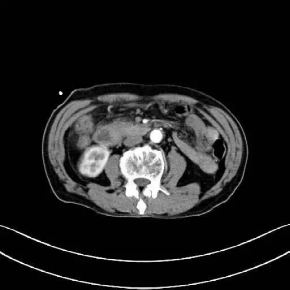

“似亲人而非亲人,带来贴心治疗!”

2019年9月25号,暨南大学附属复大肿瘤医院接到一位因腹部疼痛入院治疗的患者,姓龚,江西于都人,79岁高龄,以前曾在林场当测量工。入院通过了解,知道此患者曾在2019年9月19日-江西省于都县人民医院-腹部CT检查结果提示:胃窦部壁增厚,胆总管及主胰管轻度扩张,提示下段梗阻可能,当地医生为患者做过胆囊引流处理。通过详细的检查,龚先生被诊断为十二指肠壶腹部腺癌、上消化道梗阻。

金医生:十二指肠壶腹部腺癌起源于十二指肠乳头及乳头附近的黏膜、壶腹内的黏膜、胰管及胆总管十二指肠壁间部黏膜上皮。大部分患者早期无明显临床症状,出现症状入院检查的患者病情大部分都为中晚期。十二指肠壶腹部腺癌根治性手术难度主要在于手术切除范围大,术中吻合复杂,术后可能出现并发症多且一旦出现术后并发症就可能危及生命。龚先生入院后,我们也曾建议过行肿瘤根治性手术,但由于龚先生年纪较大,家属担心他无法耐受较大手术,不考虑行根治性手术。结合家属的要求和龚先生入院后的病情,我们综合考虑相关治疗方案,最终在杨波副主任医师和我院肿瘤外科医师共同努力下在2019年10月8日顺利完成了全麻下“胆肠吻合+胃空肠吻合+空肠R-Y吻合术”。